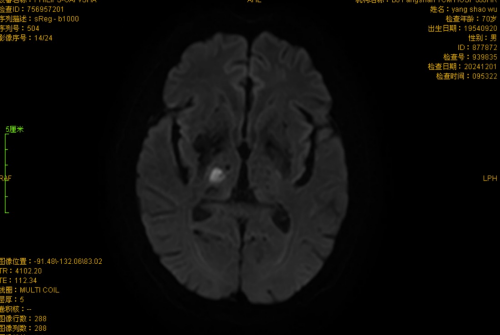

近日,一例75岁老年女性,以“右口周、右手指麻木2小时余”为主诉患者就诊于我院急诊,经卒中团队评估,考虑“丘脑梗死”,存在出现“丘脑共济失调综合症”风险,重者可致轻偏瘫,综合考虑,建议患者静脉溶栓治疗,经急诊-脑病卒中绿道联合救治,患者溶栓后右口周、右手指麻木症状消失,经住院治疗7天痊愈出院。

该类患者基本上均以口周、手足麻木起病,后续病情进展可出现偏侧共济失调和轻瘫。影像学结果均提示:丘脑新发脑梗死;既往一般认为,丘脑梗死多对患者感觉系统影响较大,未见波及共济及肌力的患者。卒中团队发现确实有文献报道丘脑腹外侧梗死所致“手口综合症”“手口足综合症”、“丘脑共济失调综合症”、“丘脑共济失调轻偏瘫”等,可能与其损伤小脑环路有关,主要责任血管归属于大脑后动脉P2段,属于后循环梗死的一种,存在致残风险;学习讨论后我们得出对仅表现为手足麻木的患者,尤其伴口周麻木者,如排除其他疾病,考虑急性脑梗死,无禁忌症应建议积极溶栓治疗、防止卒中进展致残的结论,这才有了此次救治成功的病例。